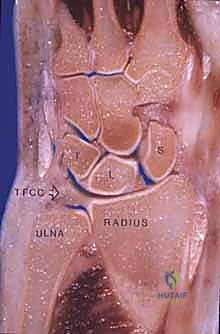

The wrist joint is a highly complex, multi-articulated structure consisting of the distal radial articular surface, the distal ulna, the triangular fibrocartilage complex (TFCC), eight carpal bones arranged into proximal and distal rows, and the bases of the five metacarpals. Four significant articulations dictate the kinematics of the wrist: the radiocarpal joint, the midcarpal joint, the carpometacarpal (CMC) joints, and the DRUJ. A sophisticated combination of interosseous, intrinsic, and extrinsic ligaments provides dynamic and static stabilization. Understanding this intricate anatomy is paramount for the arthroplasty surgeon, as the success of the implant relies heavily on restoring the native centers of rotation and balancing the surrounding soft tissue envelope.

The proximal row of the carpus (scaphoid, lunate, triquetrum) articulates with the distal radius to form the radiocarpal joint, functioning largely as an intercalated segment whose motion is dictated by the surrounding osseous contours and ligamentous tethers. The distal carpal row articulations with the metacarpal bases form the relatively rigid CMC joints. Within the distal carpal row, the primary center of wrist motion is located at the head of the capitate, slightly palmar to the geometric center of the head. This center of rotation may or may not be perfectly colinear with the third metacarpal shaft, depending on the unique anatomic variance of each patient. Proximally, the center of wrist motion lies slightly ulnar to the central axis of the radial intramedullary canal.

The sigmoid notch of the distal radius provides the articulation for the DRUJ. Strong dorsal and palmar radioulnar ligaments provide critical DRUJ stability. While earlier designs like the Re-Motion made no specific attempt to preserve the DRUJ, modern iterations and systems like the Universal 2 and Maestro feature instrumentation and radial component geometries specifically designed to preserve the DRUJ and the ulnar head. In cases where the DRUJ is irreparably damaged, many wrist replacements are performed in conjunction with ulnar head replacement arthroplasty or a Darrach procedure, though preservation of the ulnar head is always preferred to maintain the ulnocarpal ligamentous complex and provide a buttress against ulnar translation.